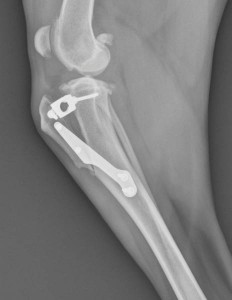

The TTA is another surgery that eliminates tibial thrust due to a torn or ruptured cruciate ligament. The TTA works by advancing part of the tibia to a 90-degree angle with the tibial plateau. This allows the muscles to keep the knee balanced and stable even with a ruptured ligament. To accomplish this, a cut is made in the tibia and the bone is then advanced. After the cut is made in the bone and the bone advanced, a special bone plate and spacer are applied with screws to allow healing.

The TTA also has a success rate of 90% –increase in muscle mass, improved knee range of motion, and improved activity levels are observed in patients. Many dogs return to the same level of activity and knee function they had before injury. Others may have some limitations with more intense activities or have intermittent knee stiffness. Regardless, an improved quality of life, greater comfort, and much improved knee function are expected in every patient following a TTA or TPLO.

When the patient is discharged some basic rehabilitation exercises are demonstrated to the client, and 14-day, 4-week and 8-week post-operative re-evaluation is required. At the 4-week recheck, the dog will be evaluated physically and the affected knee will be x-rayed to determine bone healing. The 8-week recheck is to ensure proper recovery is progressing appropriately.